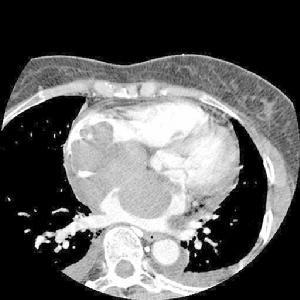

圖1 心臟轉移瘤1.迅速發展的心包積液。

4.心臟CT能了解腫瘤大小、部位,腫瘤與其他胸腔結構的關係。